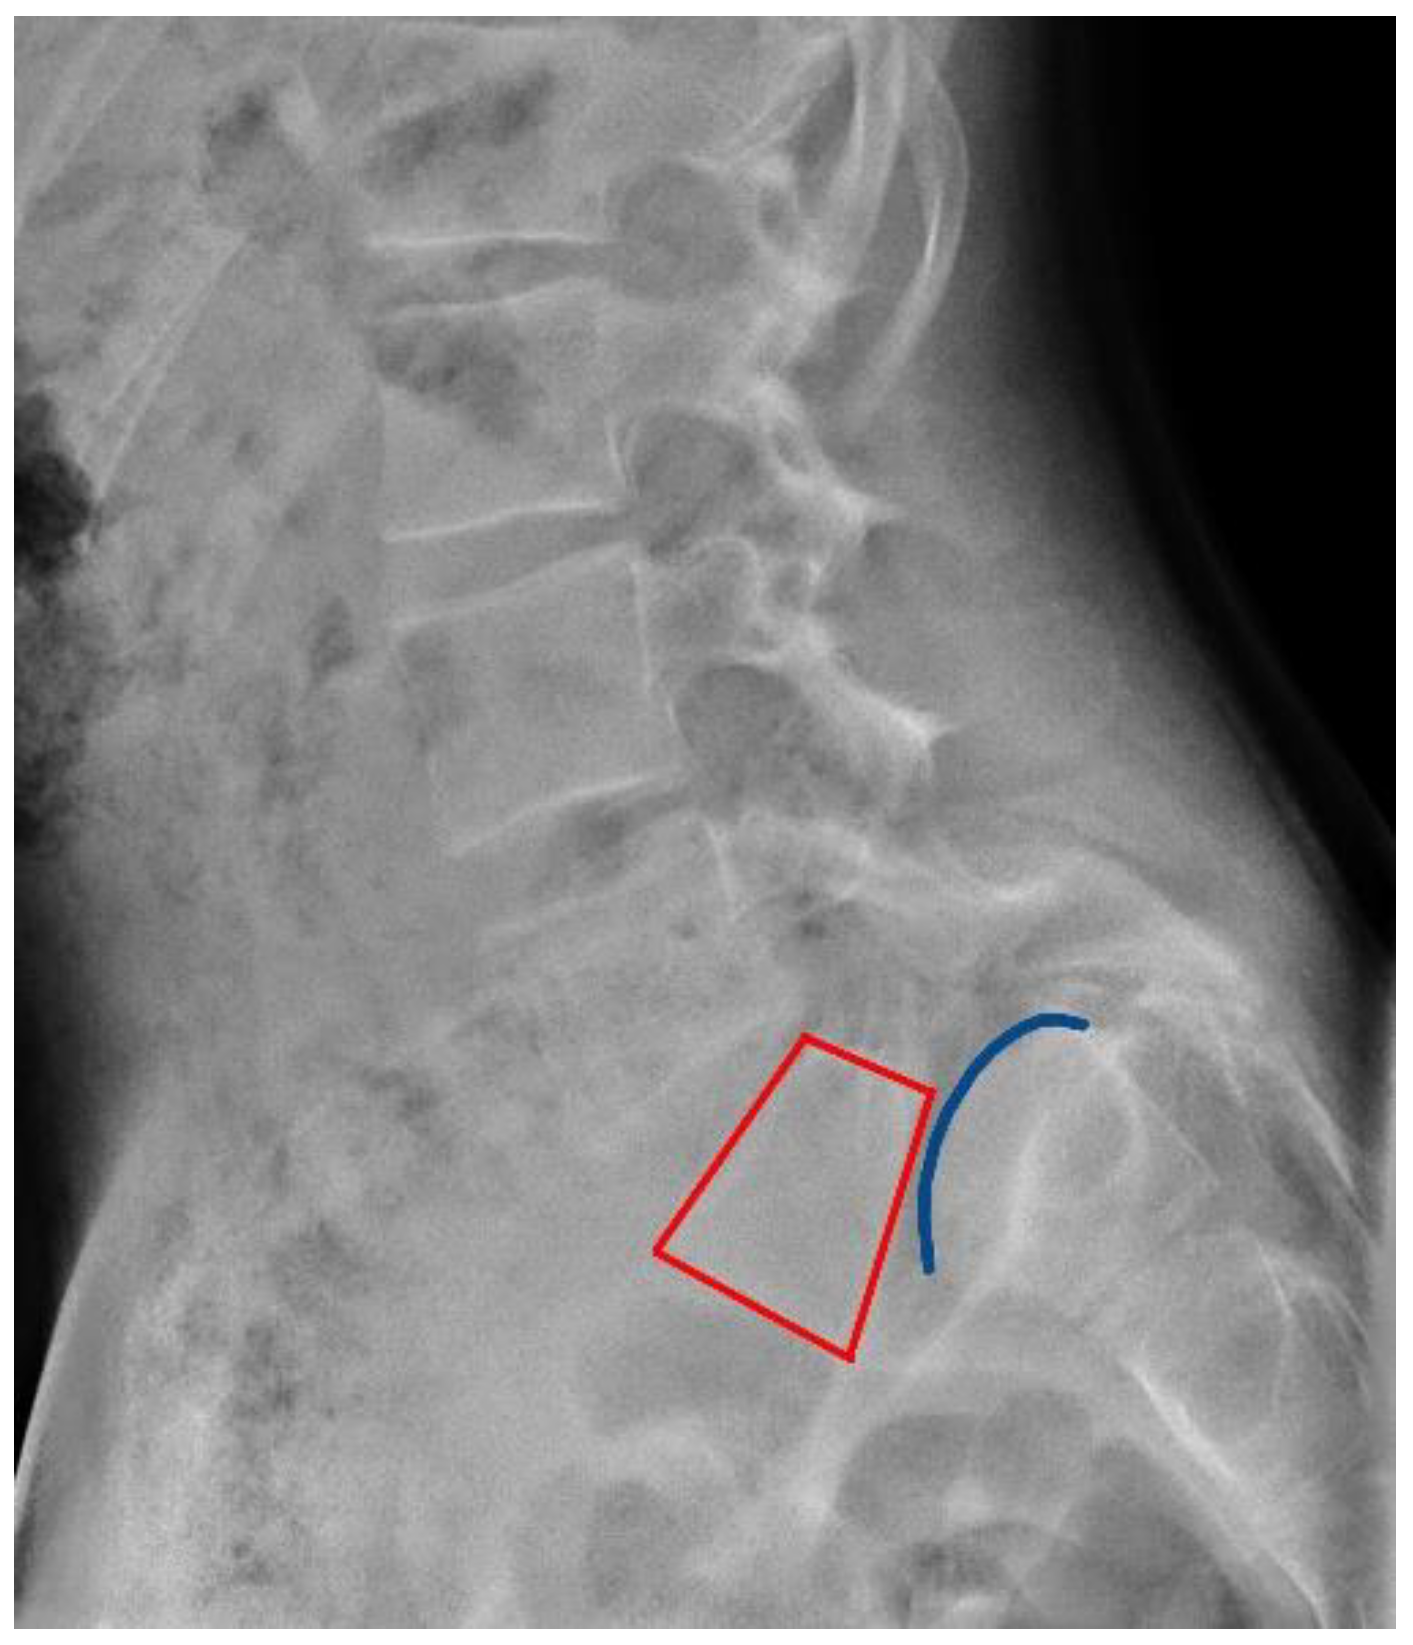

Permanent Nerve Damage Of S1. Lumbarization of S1 or lumbarization of first sacral vertebra is a condition in which the first sacral vertebra is not completely attached to its fused sacral components but instead this first sacral vertebra appears like the other lumbar vertebrae The first sacral vertebra in this instance is not joined to the remainder of the sacrum.